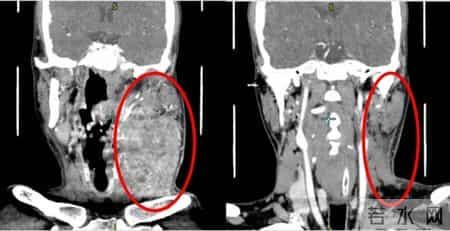

两个月前,患者许某发现左侧舌部出现溃疡,症状持续不见好转。经系统检查,他被确诊为左舌鳞状细胞癌(cT4aN3bM0)。此时,肿瘤已包绕左侧颈动脉,属于晚期高危病例,常规外科手术切除的难度与风险都极高。雪上加霜的是,患者首次就诊后,舌体肿瘤便发生破裂出血,被紧急送往上海第九人民医院急诊留观。

口腔颌面-头颈肿瘤科主任何悦教授接到首诊医生胡永杰主任医师的病情汇报后,第一时间发起首次多学科会诊,同时为患者开通诊疗绿色通道。放疗、肿瘤内科等亚专科专家共同研讨治疗方案。结合患者的病情、体质及经济状况,专家团队精准敲定“先行药物转化治疗,待肿瘤缩小后再行根治性手术”的个体化方案,采用靶向+免疫+化疗的联合治疗模式。经过规范治疗,患者肿瘤体积显著缩小,临床症状明显缓解,各项指标均达到外科手术指征,成功打破“不可手术”的僵局。